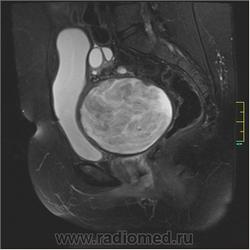

Госсипибома.

Госсипибома, или текстилома - это название группы осложнений после хирургических вмешательств в результате оставленных в теле пациента инородных предметов. Термин "Госсипибома" состоит из латинского слова gossypium (хлопок) и слова из языка суахили boma (место, где что-то спрятано), по другим данным - греческого "oma" - частицы, обозначающей опухоль. Так или иначе, госсипибома представляет собой матрикс из хлопка, окруженный гранулемой инородного тела. Термин текстилома появился позже и стал использоваться вместо термина "госсипибома", когда в хирургии вместо хлопка начали применять синтетические материалы.

Ж, 35 лет. Состояние после субтотальной гистерэктомии без придатков по поводу осложненных родов около полугода назад. Обратилась на МРТ в связи с болями и неприятными ощущениями в области малого таза.

Вот такая картинка.